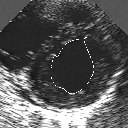

In this work, we present a new method to shape-based segmentation of deformable anatomical structures in medical images and validate this approach by detecting and tracking the endocardial border in an echographic image sequence. To this end, a global prior knowledge of the endocardial contour is captured by a prototype template with a set of admissible deformations to take into account its inherent natural variability over time. In this approach, the data likelihood model rely on an accurate statistical modeling of the grey level distribution of each class present in the image. The parameters of this distribution mixture are given by a preliminary estimation step which takes into account the distribution shape of each class. Then the tracking problem is stated in a Bayesian framework where it ends up as an optimization problem. This one is then efficiently solved by a genetic algorithm combined with a steepest ascent procedure. This technique has been successfully applied on synthetic images and on a real echocardiographic image sequence. This method seems to be particularly well suited to handle ultrasound images with strong speckle noise on which edge information cannot be exploited. Finally, the local and global minimization procedure we propose is fast, robust and do not require initialization of the template close to the desired solution. Initialization may be defined at random, leading to segmentation and tracking procedure that are completely data driven. (slides)

Figure 1:   Tracking of the endocardial contour in a medical echographic sequence at different time frames during the cardiac cycle. From top left to bottom right : frame 1, 4, 6, 9, 12, 13, 18, 20, 27, 30, 35, 40, 41, 44, 46.